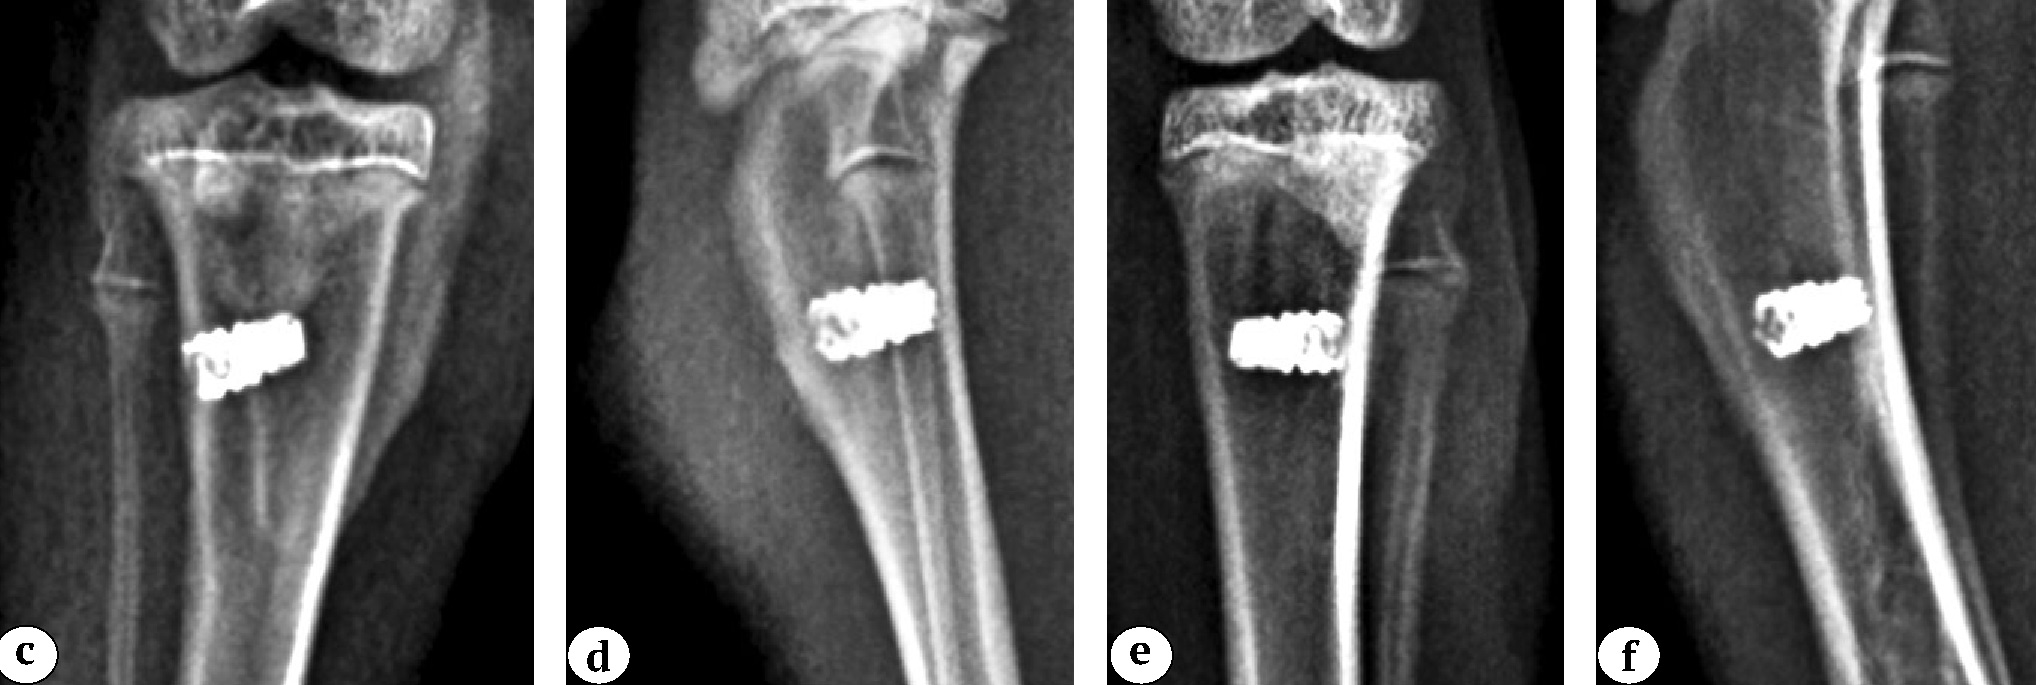

Рис. 2 (c, d, e, f). Рентгенограммы проксимального отдела бедренной кости кроликов через 4 нед. после имплантации 3D-имплантатов: c, d — титан с модификацией поверхности Ag-содержащим кальций-фосфатным покрытием; e, f — титан с модификацией поверхности Zn-содержащим кальций-фосфатным покрытием; a, c, e — левая конечность; b, d, f — правая конечность

Figure 2 (c, d, e, f). X-rays of the proximal tibia of rabbits 4 weeks after integration of 3D-printed implants: c, d — titanium with surface modification via Ag-containing calcium phosphate coating; e, f — titanium with surface modification via Zn-containing calcium phosphate coating; a, c, e — left limb; b, d, f — right limb